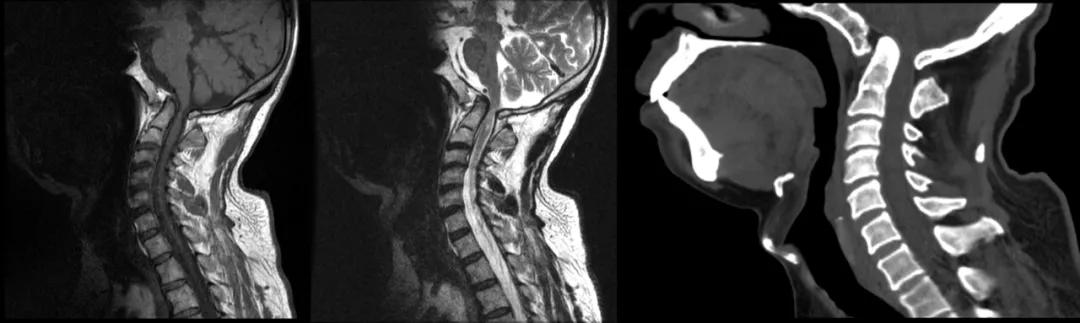

先天性颅底凹陷

先天性颅底凹陷症(Congenital basilarinvagination)是以枕骨大孔为中心的颅底骨组织、寰椎及枢椎骨质发育畸形

枕骨大孔周围的颅底骨向上方凹陷进入颅腔,并使之下方的寰枢椎,特别是齿状突升高甚至进入颅底,并引起枕骨大孔狭窄,后颅窝缩小,斜坡升高和环枕重叠等一系列畸形改变,是枕大孔区最常见的畸形

颅底凹陷症过去仅靠 X 线诊断,随着 CT 和 MR 技术的进步及普及,对该病变及合并症显示的越来越清晰

该病诊断的径线测量方法很多,但常用的是钱氏线(Chamberlain』line),亦称枕线,由硬腭后缘向枕大孔后上缘作一连线,正常人齿状突在此线 3 mm 以下,若超过即为原发性颅底凹陷症

case 1:女性,56 岁,反复头痛、头晕及双上肢麻木 5 月余。

诊断:颅底凹陷症并颈段脊髓变性。